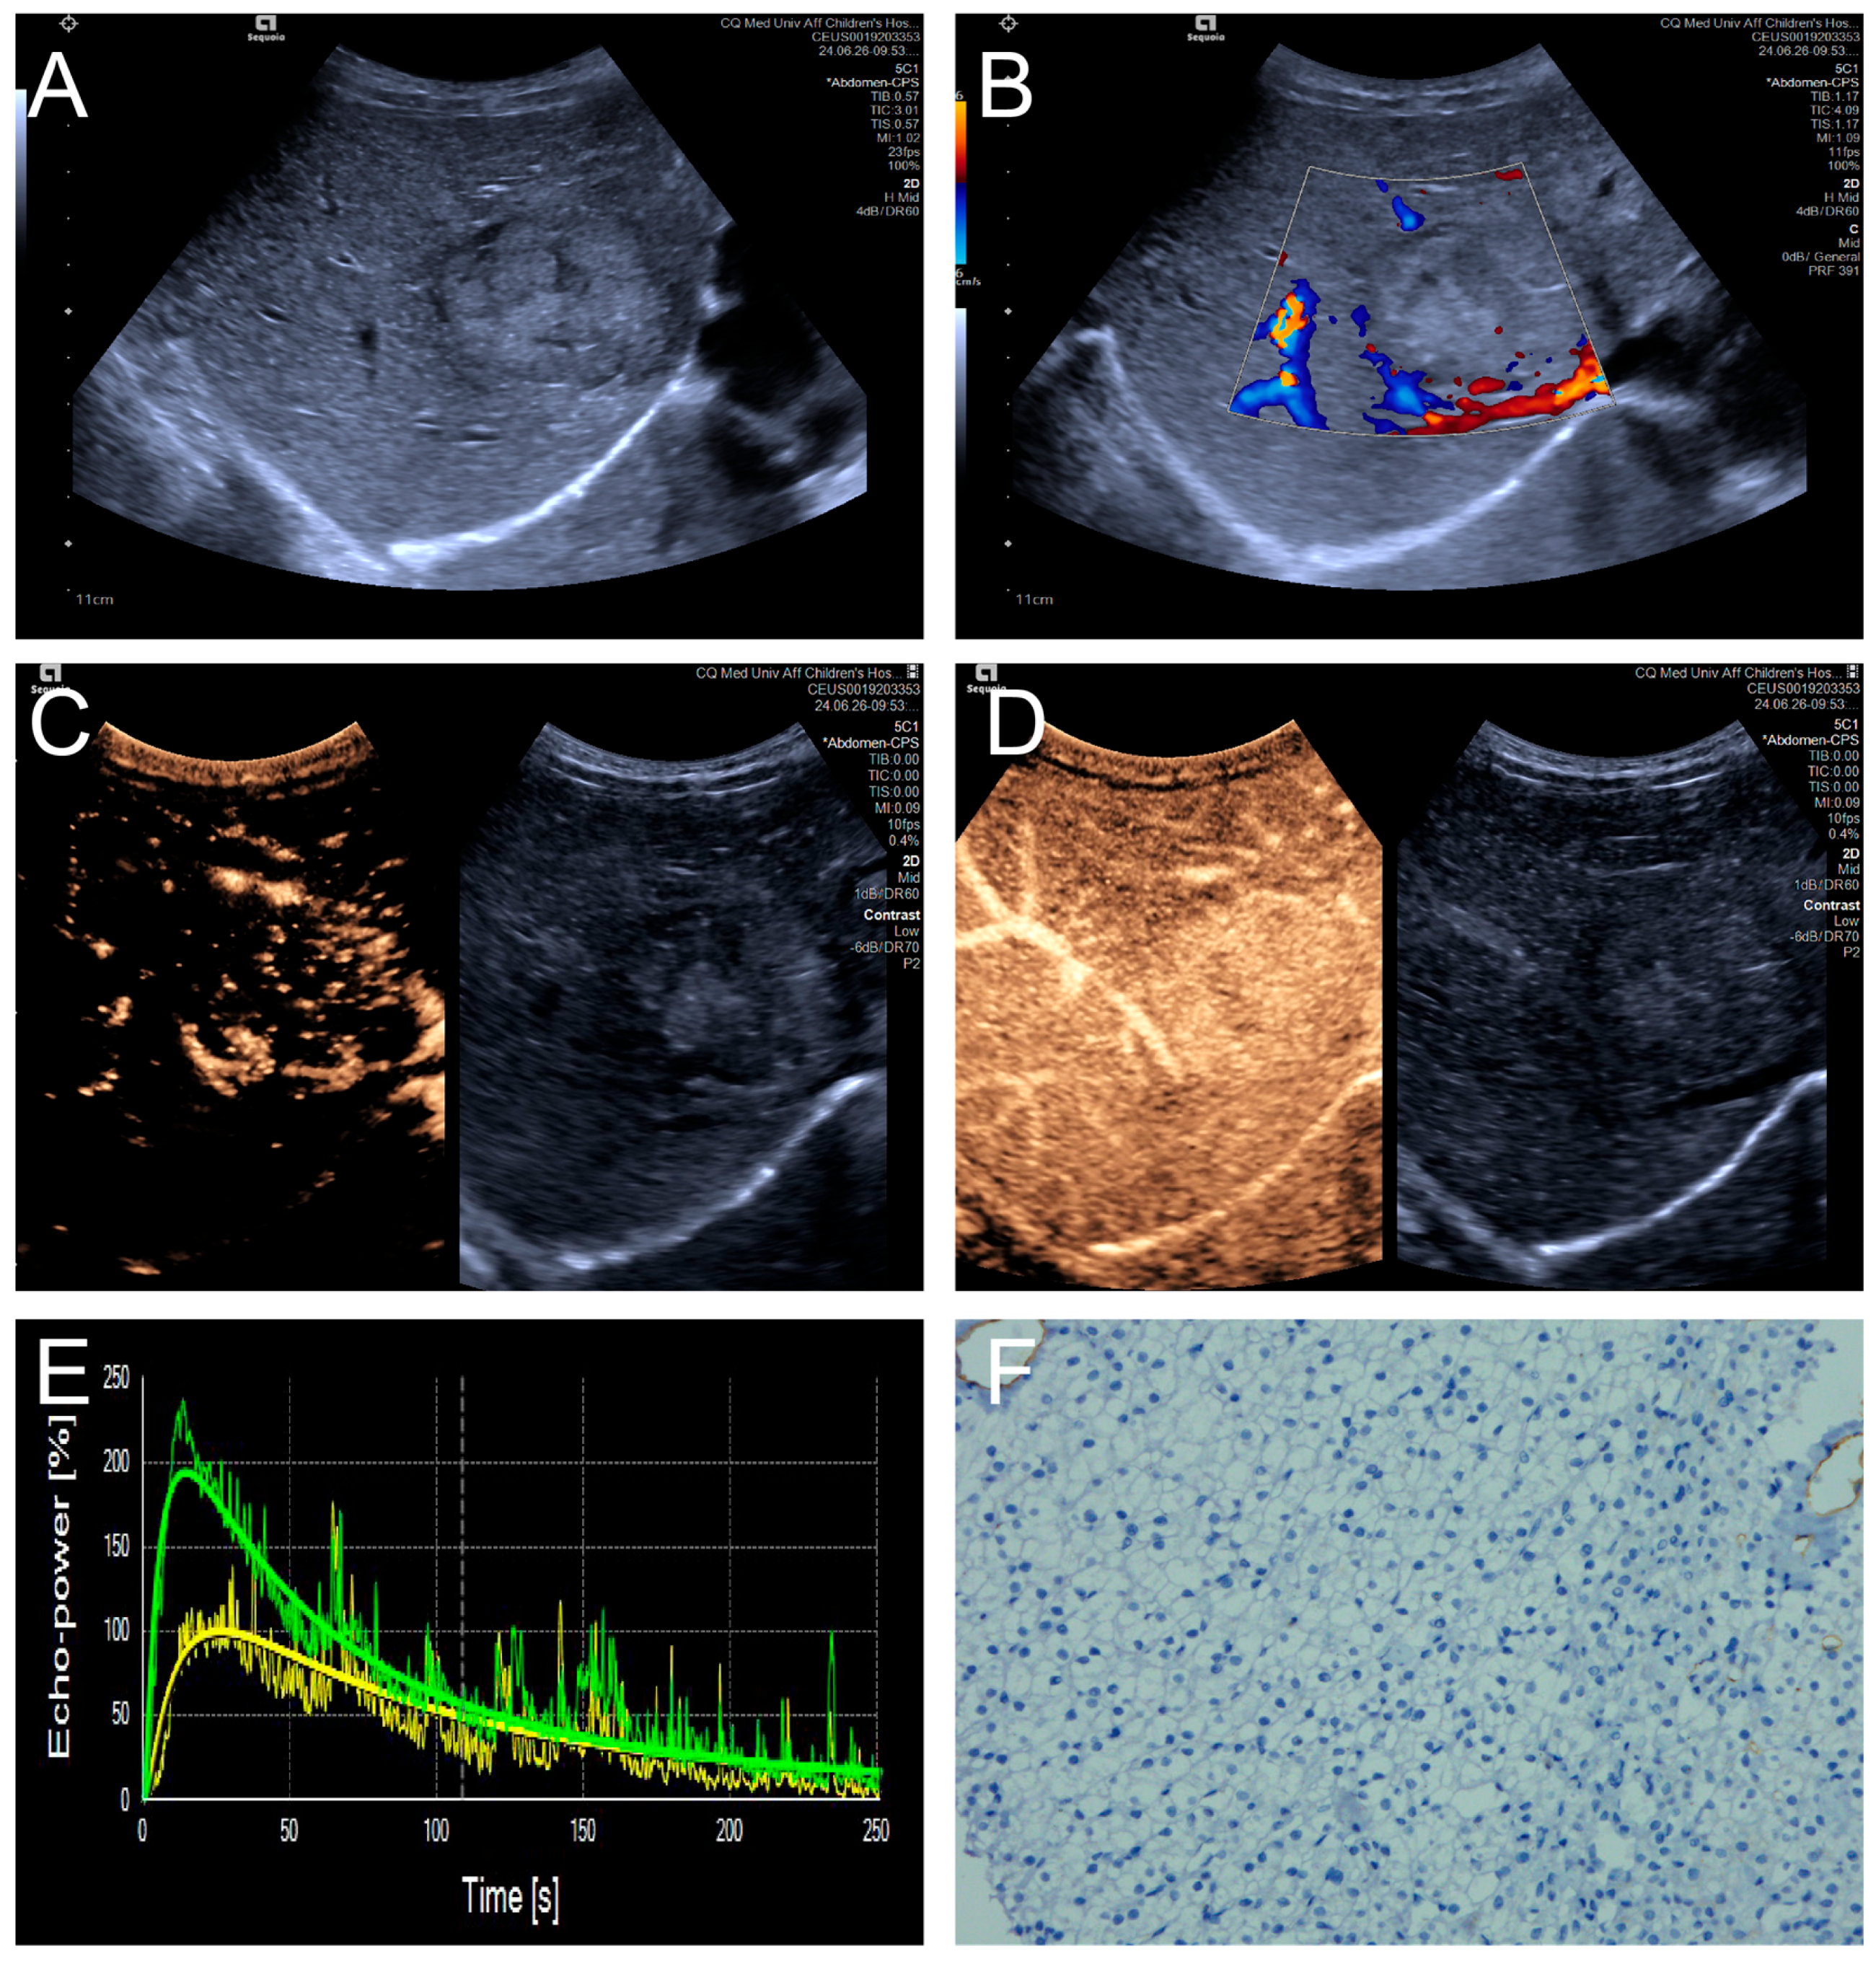

Figure 3.

(A–F) A male patient aged 4 years and 4 months with HB and low MVD. (A) The imaging revealed a well-defined mass with clear margins and hyperechoic echogenicity in the right hepatic lobe; (B) The tumor’s color Doppler flow imaging revealed distinct blood flow patterns and Adler grade I blood flow; (C,D) The CEUS exhibited uniform internal enhancement from periphery to center without any peripheral penetrating vessels; (E) TIC curves showed contrast enhancement of the lesion (green) and perfusion of the adjacent liver parenchyma (yellow). Jagged lines indicated raw signal data, and smooth lines indicated the fitted curves; (F) The biopsy specimen’s cytological immunohistochemical staining revealed few microvessels (CD34 staining × 200), and the MVD measured 21 lines/HPF.